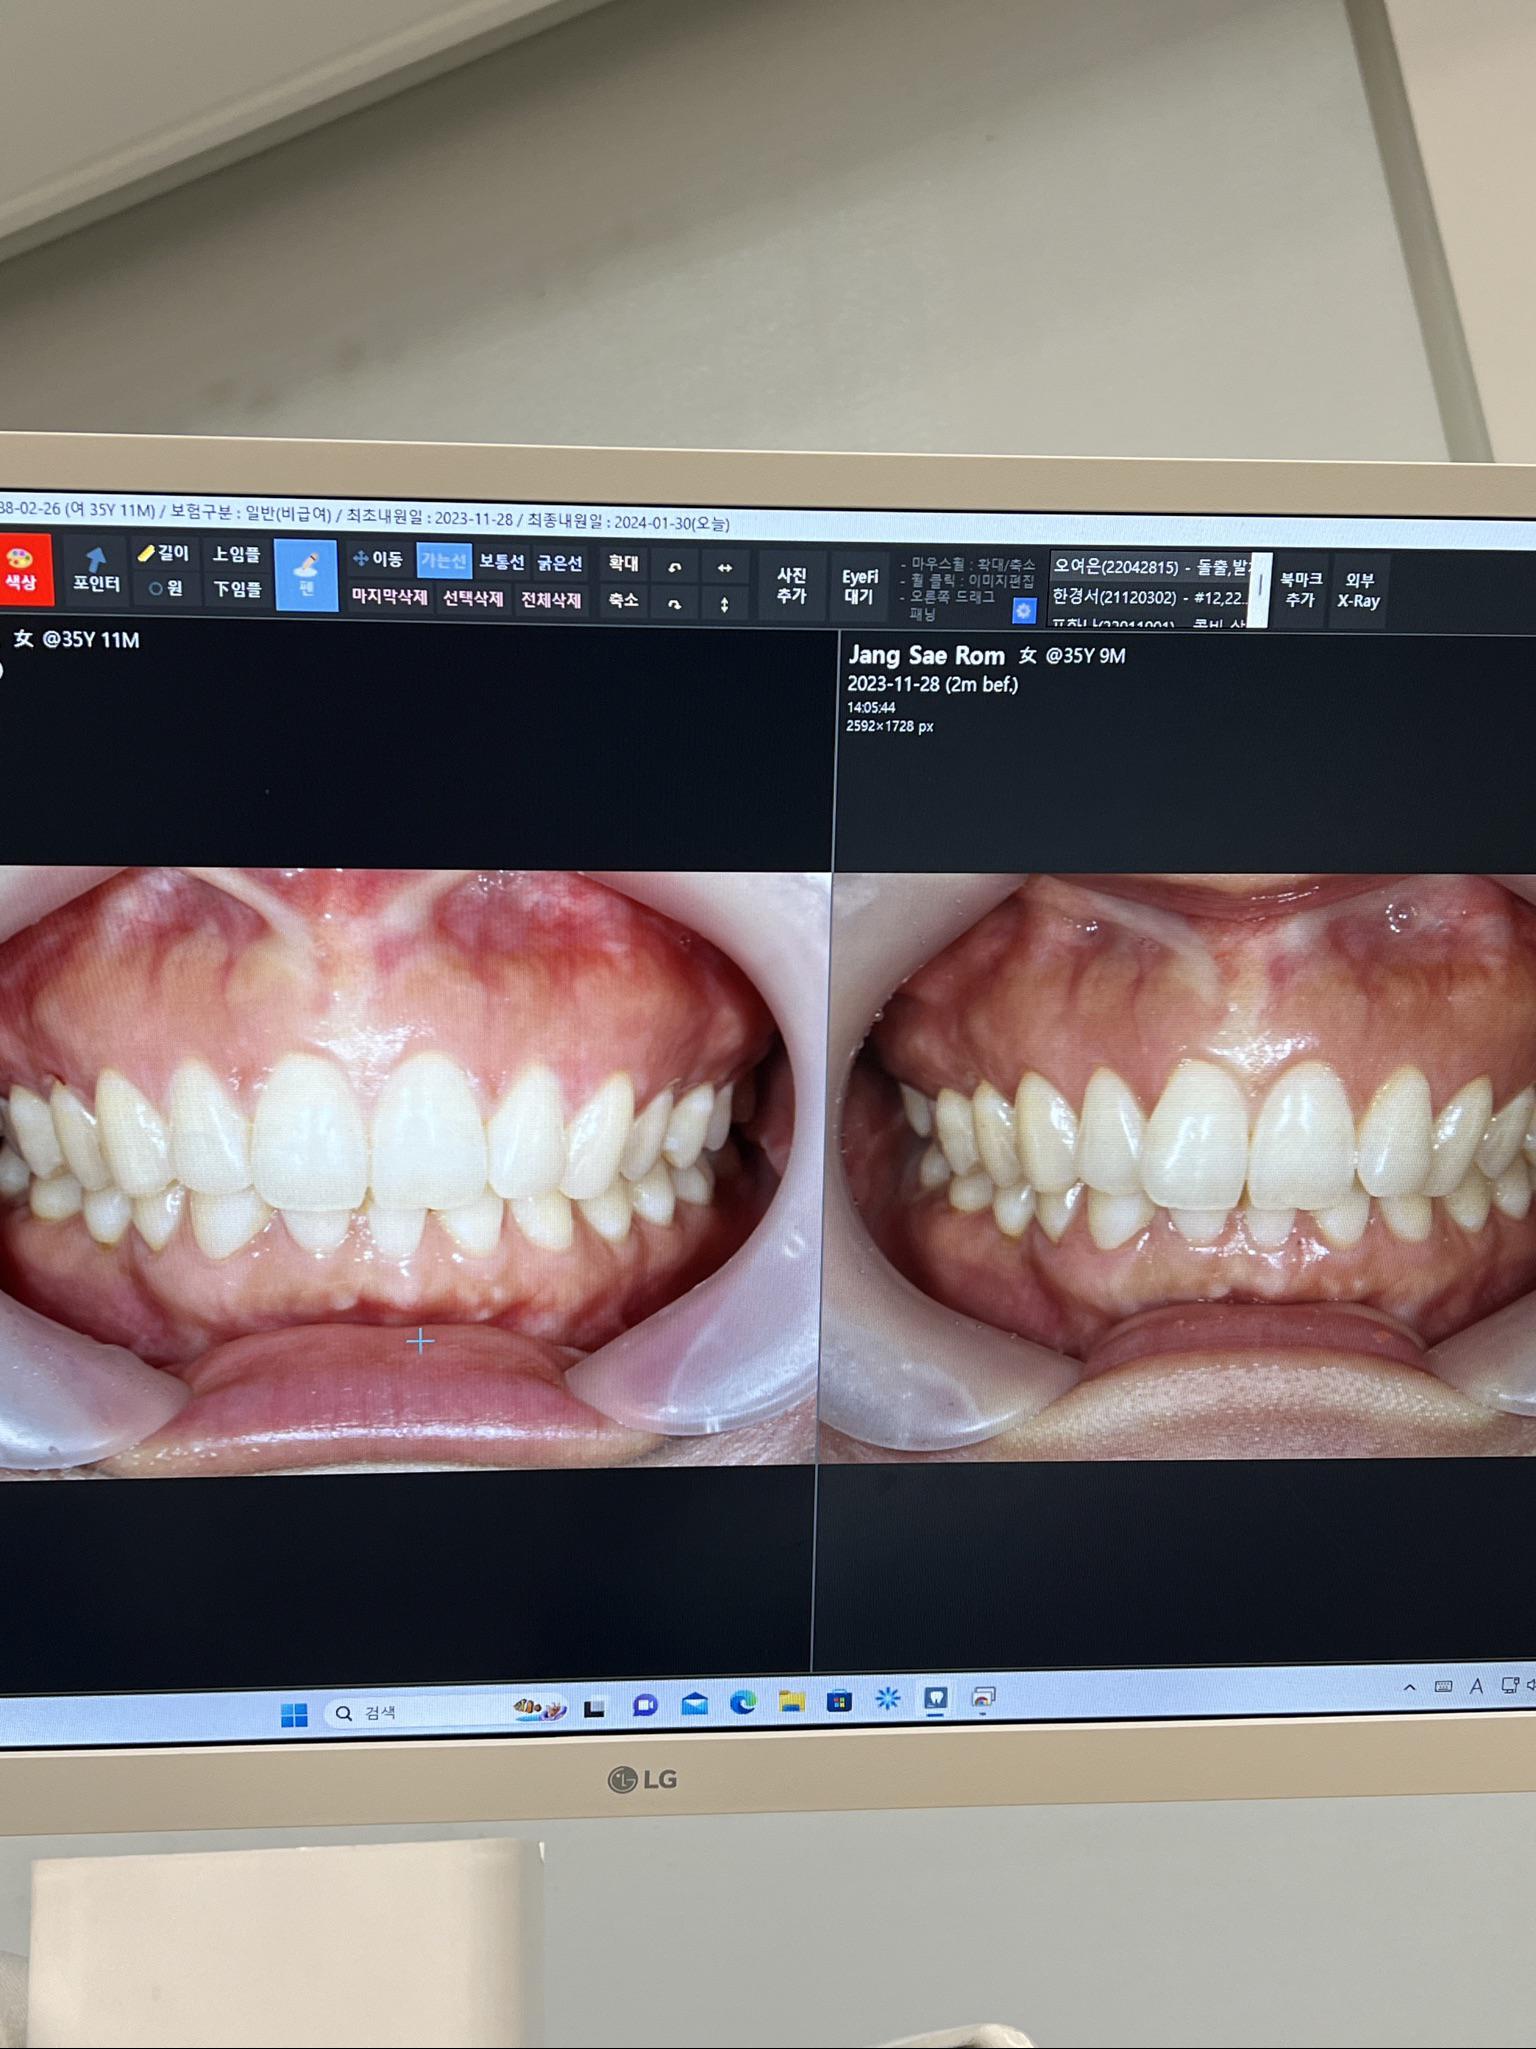

前歯部分矯正

希望の部分だけを短期間でキレイに!

前歯が気になる方へ!ご希望の部分だけをスピーディーに矯正